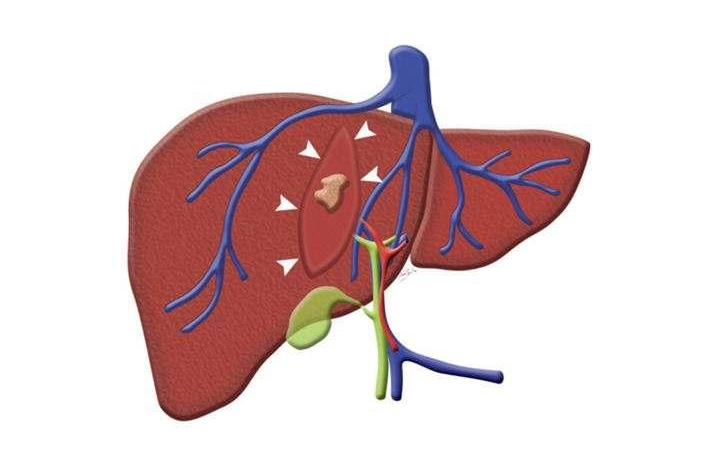

体检发现肝囊肿怎么办